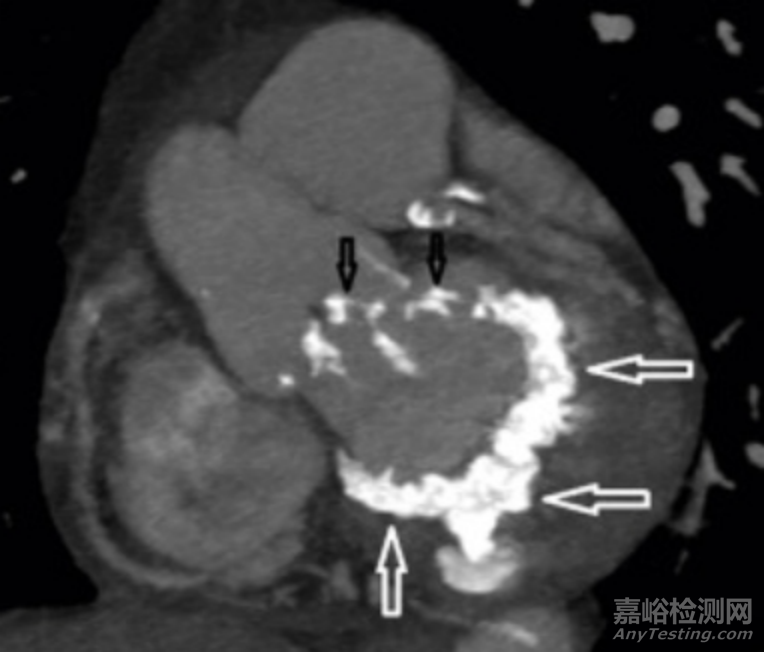

▲二尖瓣瓣環(huán)鈣化